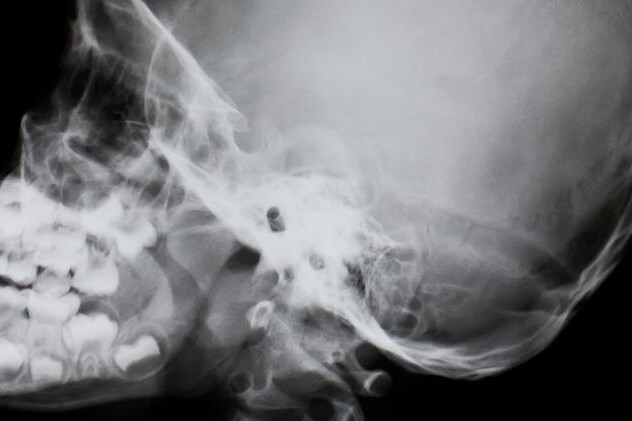

Pokud se lymfatické buňky vymknou kontrole a začnou se neomezeně dělit, hovoříme o rakovině lymfatické tkáně, neboli lymfomu. Nádory z lymfatických buněk se mohou vyskytovat v jakémkoliv orgánu, kde se tyto buňky nacházejí. Burkittův lymfom je nejčastěji lokalizován v okolí dolní čelisti nebo jiné kosti obličejové části lebky, méně často pak ve střevě, vaječníku, prsní žláze nebo ledvině. Vyskytuje se téměř výhradně u dětí a mladých dospělých a z celého světa se s ním nejčastěji setkáme v rovníkové Africe.

Africký typ se vyskytuje prakticky pouze v Africe. Postižení čelisti je mnohem častější než u zbylých dvou forem a byla prokázána jeho spojitost s infekcí virem Epstein-Barrové. Virus Epstein-Barrové, zkratkou EBV, patří do početné skupiny herpetických virů, které jsou například původcem oparu rtu či planých neštovic. EBV je kromě Burkittova lymfomu zodpovědný také za infekční mononukleózu.